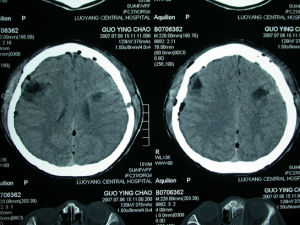

1.CT表現較複雜,瘤體可以是等密度圓形病灶,也可以是等、高混雜密度灶,也可以是不均質高密度灶,甚至僅表現為不均質鈣化灶。由於本身多因鈣化呈高密度,所以少量出血在CT圖像上較難與鈣化相鑑別。出血量大破人蛛網膜下腔時CT可以顯示。一般無瘤周水腫及占位效應,如果出血量較大,可以有輕度占位效應。增強後可以輕度或明顯均質強化,也可以不均質強化,也可以基本無強化。2.血管造影表現腦實質內的海綿狀血管瘤腦血管造影常常無異常發現。硬腦膜海綿狀血管瘤可以表現為富血供結節,延遲可見局部毛細血管染色,偶可見供血動脈和引流靜脈。

結果2.1CT和DSA表現:23例均作CT平掃,9例CT增強掃描,共發現20個病灶,CT平掃CA表現為略高密度病變,較小病灶呈等密度,1個病灶內CT可見極高密度鈣化,呈斑點狀或小塊狀,9例行CT增強掃描呈輕度到中度強化者12個病灶,5病灶未見強化,3個明顯均勻強化,1例合併腦血腫者呈高密度,但其密度不均,並有周圍水腫。8例腦行DSA檢查者,未見增粗供養動脈和引流靜脈,6例瘤巢未顯影,2例瘤巢在靜脈期輕度染色,4例較大腦CA見瘤巢鄰近血管受壓移位。

2.2MRI表現:23例病人單發19例,占83%,其餘4例為多發病灶。共發現29個病灶,MRI檢查明顯優於CT。位於腦幹1個,小腦5個,大腦半球23個。MRI檢查行T1WI和T2WI、DWI、CRE序列。23例腦海綿狀血管瘤6例位於顳葉,5例位於額葉,9例位於頂葉和基底節區,1例位於腦幹,2例位於小腦。最多1例病人腦部可見3個病灶。病灶最小約0.3cm,最大約3.5cm,邊界清楚,不規則,均呈類圓形或結節狀。1個病灶呈T1WI、T2WI都呈高信號,13個病灶T1WI和T2WI均呈高、低混合信號,高、低信號比例和形態各異。T2WI28個病灶周圍均可見黑色低信號環影,7個病灶呈線條狀環,3個病灶呈條片狀環。所做的病例DWI序列顯示病灶7個呈均勻黑色低信號,2個病灶呈中間混有高信號的不均勻黑色低信號,病灶同周圍腦組織境界較清楚。病灶內未見異常血管流空信號,15例做3D_MRA成像,未見有供血動脈影像,僅2例較大CA顯示腦動脈移位及抱球狀改變,瘤巢在3D_TOFMRA背景上仍呈高信號,而非動脈血流之高信號,這是因為3D_TOFMR不能消除圖像背景上原瘤巢的高信號所致,不能明確診斷。

3.2腦內海綿狀血管瘤主要影像診斷方法:MR問世以前,腦內海綿狀血管瘤主要靠CT診斷,可以顯示急性出血,呈高密度影,但無特異性,病灶較小的常常不能發現,大部分不能明確診斷,診斷缺乏敏感性和特異性。本文8例做3D_MRA成像,5例做DSA檢查,均未發現異常的供血動脈,所以MRADSA檢查,對腦內海綿狀血管瘤均不能發現病灶。MR多序列和多方位的檢查及腦內海綿狀血管瘤有一些特異性的征像,可以明確診斷海綿狀血管瘤的部位、大小及形狀。